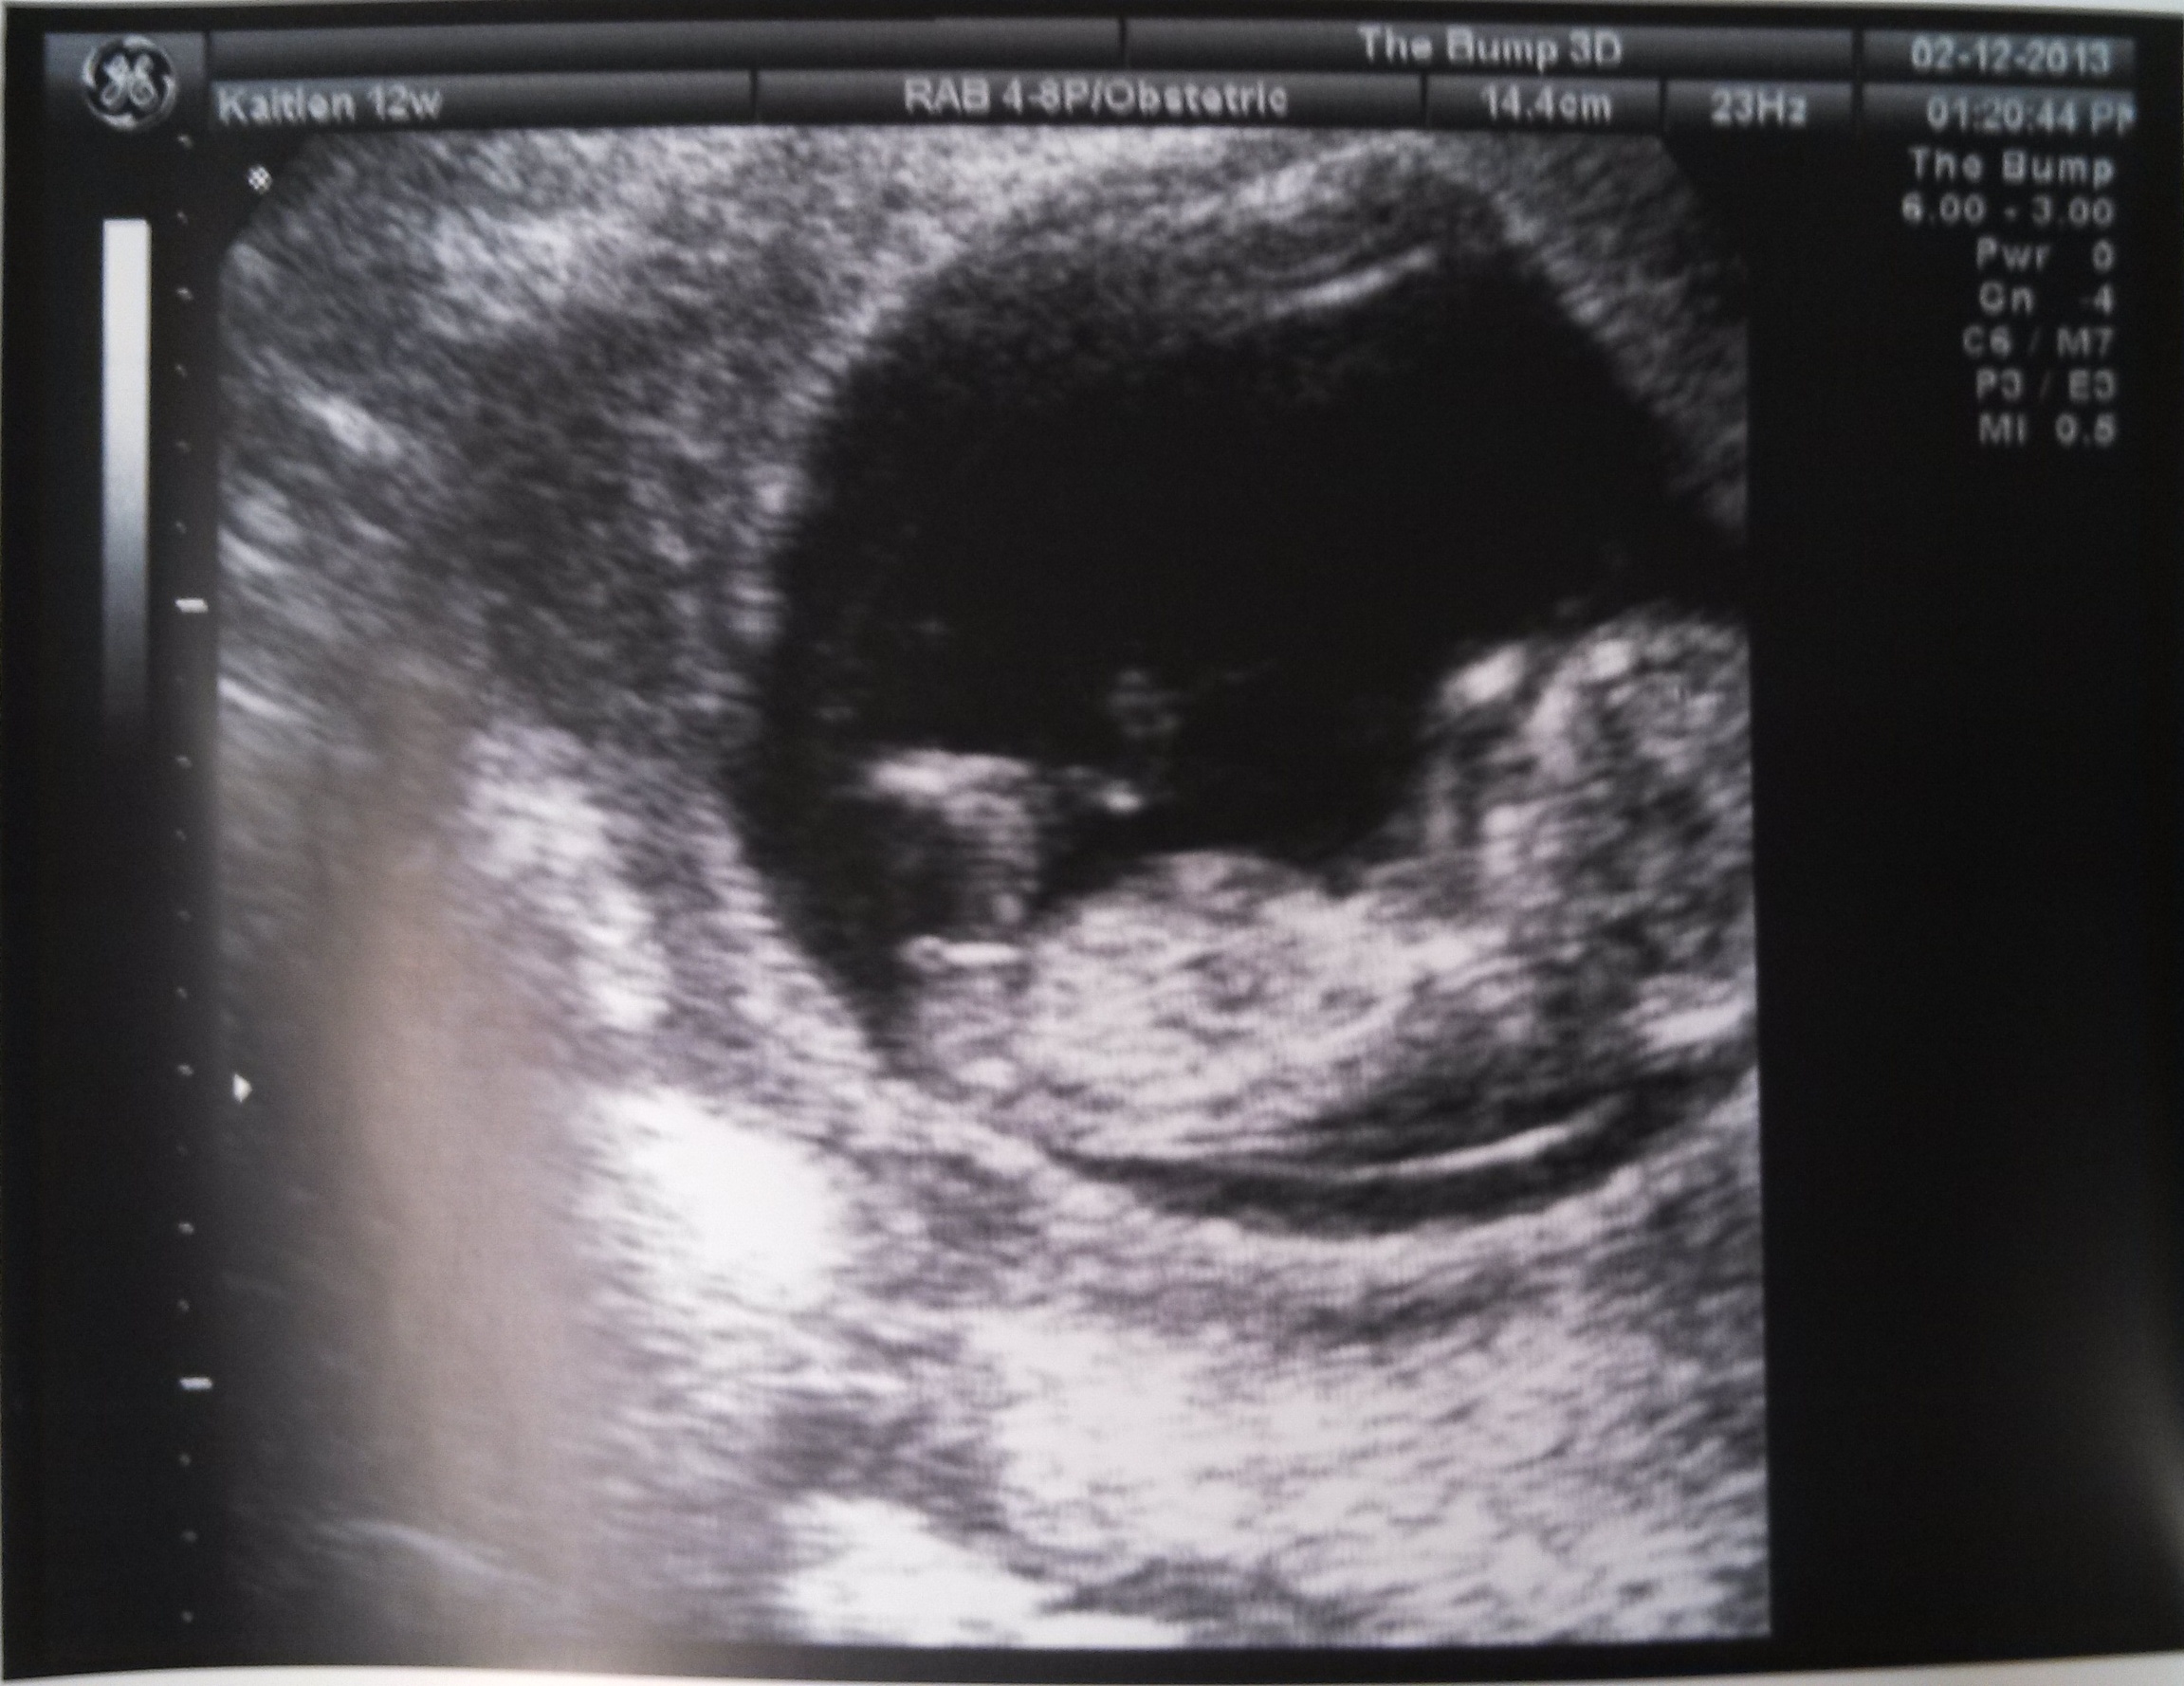

My daughter is 12 weeks pregnant and she had an ultrasound a few days ago. From reading about the nub theory, I think this should be a girl...but some of the confirmed boy 12 week ultrasound pics I've seen on here, look similar to these pics too! What do you all think??Attachment 9003Attachment 9004Attachment 9005